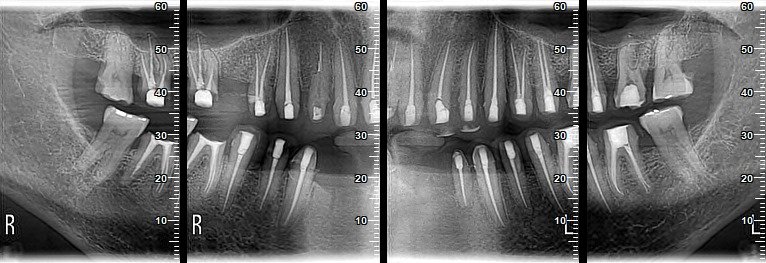

L’endodontie fait partie des spécialités de dentisterie qui s’intéressent au tissu vivant de la dent, appelé « pulpe ». Le traitement endodontique (la dévitalisation) est réalisé lorsque la carie dentaire ne peut pas être traitée.

L’objectif du dentiste est de préserver une dent précédemment endommagée (préservation de la dent), car le traitement du canal radiculaire est un traitement dentaire conservateur en endodontie ou en endodontologie. Ce traitement est souvent désigné par le terme anglais endodontic treatment.

Il vise à préserver la dent, même si la pulpe dentaire est morte et que la dent est dévitalisée. Un traitement de canal est également effectué si la dent est encore vitale, mais déjà fortement enflammée (on parle alors d’inflammation dentaire) et irréversible (non réversible). Cependant, il est possible qu’une douleur dentaire apparaisse après un traitement de canal, car la douleur du parodonte est typique d’une dent fraîchement traitée par le canal radiculaire.

Une dent saine se compose d’une couronne dentaire visible et d’une ou plusieurs racines. À l’intérieur de la couronne et de la racine de la dent se trouve ce que l’on appelle la pulpe ou le nerf dentaire. Celui-ci se compose de tissu conjonctif, de vaisseaux sanguins et lymphatiques ainsi que de fibres nerveuses. La pulpe saine réagit aux irritations, qui peuvent être déclenchées par des caries ou des blessures, en provoquant une inflammation. Si un traitement dentaire est effectué rapidement, par exemple en éliminant les caries et en réalisant une obturation ou une couronne artificielle, l’inflammation peut se résorber. En l’absence d’intervention précoce, l’inflammation de la parodontite peut progresser, entraînant une gingivite (stomatite dentaire). Celle-ci peut être associée à de graves douleurs dentaires, car au départ, un nerf dentaire irrité provoque des douleurs, lesquelles surviennent toujours lorsque le nerf est irrité, car le nerf se trouve à l’intérieur de la dent.L’inflammation peut entraîner la mort de la pulpe et provoquer une infection bactérienne des canaux radiculaires ou un abcès.Les toxines sécrétées par les bactéries buccales migrent alors dans les tissus autour de la pointe de la racine dentaire, provoquant souvent des réactions chroniques sous forme de granulome ou de kyste. Dans le pire des cas, les bactéries peuvent infecter le tissu osseux au niveau de l’extrémité de la racine, provoquant des abcès purulents et une joue épaisse.